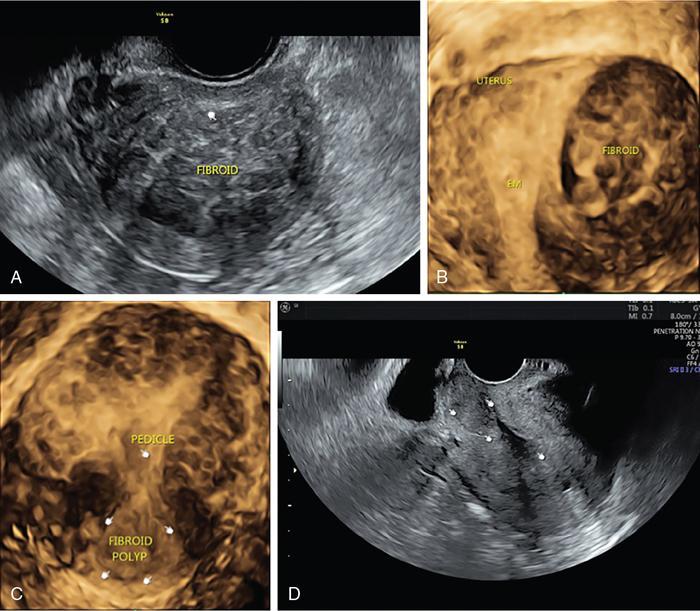

John De Lindsay, Sumathy, Vasumathy, Usha nandhini Ganeshan, N. Sundari ENDOMETRITIS Endometritis is defined as the inflammation of the uterine endometrial layer. Endometritis is frequently observed in the pregnant and postpartum population. Pelvic inflammatory disease (PID) and invasive gynaecological procedures are the most common causes of acute endometritis in nonobstetric population. Endometritis is the most complex asymptomatic and often presents with subclinical form of PID. Ultrasound may reveal minimal particulate endometrial fluid with mildly thickened endometrium showing increased vascularity. Computed tomography (CT) findings include a diffusely bulky uterus due by inflammation, mild fluid distension of endometrial cavity and striking endometrial enhancement in comparison to the adjacent myometrium due to mucosal hyperaemia. ‘Indistinct uterine border’ sign is observed in patients with endometritis, which is defined as the loss of distinction between the uterus and the adnexa. Since it is also observed in the cases of endometriosis or malignancy, it is a nonspecific sign. The age of the patient, clinical presentation, and the biopsy of endometrium helps in differentiating endometritis from other pathologies. UTERINE ARTERIOVENOUS MALFORMATION Uterine arteriovenous malformation (UAVM) is an abnormal connection between the arteries and the veins of the uterine myometrium without an intervening capillary bed. They were first reported by Dubreil and Loubat in 1926. They can be congenital or acquired. Even though UAVMs have varied presentation, uterine bleeding is the most common one. They often follow a pregnancy event. Episodic or occasionally torrential vaginal bleeding can occur. Congestive heart failure secondary to vascular steal can be a rare presentation due to a large UAVM. UAVM is most commonly an acquired condition. Pregnancy has a significant role in their pathogenesis. It is most commonly observed in reproductive age group. UAVMs are frequently observed in the postpartum period, few months after spontaneous miscarriage, surgical evacuation of uterus for miscarriage or medical termination of pregnancy. Infection, inflammation, retained products of conception (RPOC), gestational trophoblastic disease (GTD), gynaecologic malignancies, pelvic trauma and exposure to diethylstilboestrol can also lead to UAVMs. Few cases are also reported in young adolescent and postmenopausal females. UAVMs rarely are congenital and may be also associated with AVMs in other locations. Congenital AVMs Congenital AVMs have a central nidus with multiple feeding arteries and draining veins. In this condition, there is extension of the lesion beyond that uterus and multiple pelvic vessels other than uterine vessels draining into them. That cause of congenital AVMs are thought to be due to failure of embryological differentiation. With the progression of pregnancy, these vessels have the propensity to invade surrounding structures. Iatrogenic Acquired AVMs When the venous sinuses are incorporated into the scars of myometrium after the necrosis of chorionic villi, acquired malformations may arise. In contradiction to congenital AVMs, acquired AVMs multiple fistulous communication between the intramural arteries and the venous plexus. These AVMs may have either dual blood supply or a single supply from the uterine arteries and presents without nidus. Vaginal bleeding caused by pregnancy-related causes must be differentiated from UAVMs. Surgery/evacuation is the appropriate management for the former and the same is contraindicated in the UAVMs and hence an accurate definitive diagnosis is important. Grey-scale ultrasound findings are nonspecific and they are subtle heterogeneity of myometrium with multiple tubular or ‘spongy’ anechoic or hypoechoic areas. In spite of varied presentations such as an intramural uterine, endometrial or cervical mass-like lesions or prominent parametrial vessels, it has minimal mass effect. On colour Doppler, within the myometrium, a region of increased vascularity and most commonly with aliasing is seen. A group of vessels traversing the myometrium running perpendicular to and into the endometrium, from the arcuate vessels, can be seen. It is not specific, as they are also observed in RPOC, GTD, placental polyp and vascular endometrial neoplasm. In pulsed Doppler, multidirectional turbulent flow with intense vascularity can be seen with high peak velocity (mean peak systolic velocity [PSV] = 136 cm/s) and low resistance (mean resistance index = 0.3) flow. The arteries have low pulsatility while the draining veins are pulsatile and show high velocity flow. Magnetic resonance imaging (MRI) offers noninvasive confirmation of the diagnosis of UAVM. T1-weighted and T2-weighted images show multiple serpentine signal voids along the uterine wall, endometrial cavity and parametrium. Contrast-enhanced MR angiography shows intensely enhancing complex serpentine abnormal vessels with early venous return. Catheter angiography can be reserved only for women who require embolization of the AVM. The consent for both diagnostic angiography and therapeutic embolization should be obtained simultaneously to avoid repeat therapeutic procedures. Management of UAVM depends on: UAVM can be treated with medical therapy with hormones, uterine artery embolization or with definitive hysterectomy. Once the diagnosis of a UAVM is confirmed, the treatment option depends on the clinical condition of the patient. The size of the AVM bears no correlation to the need for embolization. Timmerman et al. found that AVMs having PSV of at or above 0.83 m/s, most often requires embolization. Also, the vascular malformation with PSV value below 0.39 m/s does not require embolization. Placental bed subinvolution, enhanced myometrial vascularity (EMV), molar pregnancy or RPOC are the other causes of uterine mass vascular malformations which usually has a mean PSV of 0.52 m/s and does not require embolization. Transcatheter targeted uterine artery embolization is indicated in selected cases, if bleeding persists to a degree that blood transfusions are required to maintain haemodynamic stability or multiple repeated acute hospitalizations. This is preferred over surgical management owing to its immediate minimally invasive and fertility sparing benefits. Gelfoam had been suggested earlier as the material of choice for embolization. Various other embolic materials like polyvinyl alcohol, Histoacryl glue, stainless steel coils, detachable balloons, and haemostatic gelatin are also used nowadays. Normal intrauterine pregnancies after embolization have been reported, proving that an adequate collateral blood supply can develop to support a full-term pregnancy. Gestational Trophoblastic Disease RPOC: Presence of endometrial pathology rather than myometrial origin. FIBROIDS Leiomyomas, also known as fibroids or myomas, are the most common gynaecologic neoplasms, occurring in 20%–30% of women of reproductive age. Symptomatic uterine fibroid accounts for about 30% of hysterectomies performed for women older than 18 years of age and 41% of hysterectomies performed for women from 44 to 64 years of age. Leiomyomas are the benign neoplasms made up of whorled fascicles of smooth muscle and fibrous connective attached to the uterine muscular wall. Even in the absence of true capsule, leiomyomas are well circumscribed and contains a pseudocapsule. Its size is variable, ranging from tiny microscopic to large tumours filling the abdomen. Most commonly, the uterine leiomyomas are seen in the myometrium of uterine corpus. However, it is also seen in the cervix (<5% of cases). On the basis of the location, uterine fibroids are classified as submucosal, intramural or subserosal. This classification is of clinical significance because the symptoms and treatment vary among these subtypes of leiomyomas. Submucosal myomas are further subclassified as 0, I and II depending on the percentage within the endometrial cavity. The first two categories can be removed hysteroscopically (Table 11.15.3.1). Pedunculated leiomyomas are attached to the uterus by a stalk and may be either intracavitary or exophytic (narrower than 50% of diameter of myoma). Rarely, a submucosal fibroid may grow pedunculated and extends into the cervical canal or vaginal canal and its prevalence is about 2.5%. Pedunculated subserosal leiomyomas may undergo torsion, resulting in infarction accompanied by pain. Lateral growth into broad ligament leads to intraligamentous leiomyoma (Table 11.15.3.1). Rarely, a pedunculated leiomyoma may become detached from the uterus (parasitic leiomyoma). Depending on the location, size and number of uterine fibroids, it has varied presentation. Symptoms caused by leiomyomas are classified into three different categories such as abnormal uterine bleeding, pelvic pressure and pain and reproductive dysfunction. Submucosal leiomyomas and intramural leiomyomas are often associated with menorrhagia (Table 11.15.3.1). Because of leiomyoma, uterus may be irregularly shaped and causes symptoms based on their locations. Anterior leiomyomas cause urinary symptoms, whereas the posterior leiomyomas cause constipation. Ureter may be compressed by broad ligament leiomyomas and presents as hydroureter or hydronephrosis. In case of degeneration or torsion of a pedunculated leiomyoma, acute pain may be the presentation. Leiomyomas are an infrequent primary cause of infertility. Malpresentation, pregnancy failures and dystocia are reported. Ultrasound is the first-line imaging modality because it is a cost-effective portable real-time examination that provides good anatomic detail. Leiomyomas appear as a well-defined round or oval hypoechoic solid mass. It is mostly associated with posterior shadowing possibly due to calcifications or interface of the margins of the leiomyoma with the normal myometrium. Degeneration or lipoleiomyoma can be suggested when there is internal echo-poor or hyperechoic foci, respectively. The presence of hypervascularity in a large solitary uterine mass can identify suspicious masses, such as a leiomyosarcoma (LMS). Another study found that there is an increased detection rate of uterine sarcomas while using a cut-off value of 41 cm/s. In the assessment of a uterus enlarged with multiple leiomyomas, ultrasound has FOV limitations. Likewise, it has limited role in the assessment of retroverted uteri, pedunculated subserosal myomas and concomitant adnexal processes. Little has been reported regarding sonographic changes after MR HIFU and uterine fibroid embolization (UFE). Differential diagnosis has been discussed in Table 11.15.3.2. Hyperechoic unlike a myomatous polyp which appears hypoechoic Heterogeneous endometrium with little mass effect Enlarged uterus and a deformed contour are the most common computed tomography (CT) findings. Even though CT is the primary modality for the staging of cancers, it has limitation of reduced contrast resolution for the assessment of focal myometrial masses, and associated with risk of ionizing radiation. Also, in delineating the zonal anatomy for accurate localization of leiomyomas and LMSs, CT is inferior to magnetic resonance imaging (MRI). More often dense or amorphous calcification is seen. Almost exclusively, on plain radiography or CT, these patterns of calcification favours the diagnosis of leiomyoma. Ring-like calcification at the margins of a leiomyoma is a rarely observed pattern, which represents the thrombosed veins. Positron emission tomography (PET)/CT is an ideal modality for the confirmation of malignancy and also helps in detection of metastasis and recurrence. In a small study of patients with histopathologically confirmed uterine sarcoma found that on comparing with the findings of MRI and ultrasound with power Doppler imaging, the results of fluorodeoxyglucose (FDG) PET examinations were 100% positive. However, it has limitations such as increased false-positive rate and reduced widespread availability. MRI appearance of leiomyomas: MRI is considered as the most accurate imaging technique for the detection and localization of leiomyomas. In determining the presence and location of leiomyomas in infertile women before myomectomy, MRI has been shown to be more accurate and sensitive than US or hysterosalpingography. Nondegenerated uterine leiomyomas usually has a typical MRI appearance of (Table 11.15.3.4) well-circumscribed masses with homogeneously decreased T2-weighted signal intensity. TABLE 11.15.3.3 Note: SI, signal intensity; ADC, apparent diffusion coefficient. Compared with that of normal smooth muscle myometrium. Degenerated leiomyomas have varied imaging appearances on T1-weighted, T2-weighted and contrast-enhanced images as described in Tables 11.15.3.4 and 11.15.3.5. Hyaline Oedema *Common *50% cases *Usually peripheral Cystic Myxoid Carneous, red, or UAE associated Calcific Leiomyoma variants (Tables 11.15.3.4 and 11.15.3.6): There are several, such as mitotically active, cellular and atypical leiomyomas, as well as smooth muscle tumours of uncertain malignant potential (STUMP). On histopathological examination, the nondegenerated fibroids are made up of goals of uniform smooth muscles with varied amounts of collagen. Cellular leiomyomas, which are composed of compact smooth muscles cells only with no collagen, will demonstrate increased T2-weighted signal intensity and homogeneous enhancement. There is a greater risk of recurrence in case of atypical leiomyomas and uterine STUMP. The patients who had undergone myomectomy and were found to have atypical leiomyoma, must be under surveillance with an annual pelvic ultrasound or MRI. Since the recurrences may presents as pelvic or abdominal masses or as pulmonary metastases, for all the patients with STUMP lesions, routine physical examinations, including pelvic examinations and the baseline CT of the chest, abdomen and the pelvis are recommended for every 6 months for 5 years and then annually thereafter. In addition, prompt re-exploration and staging is recommended for patients with STUMP who have undergone a morcellation myomectomy. An aggressive imaging surveillance is considered, when the disease is present. Atypical leiomyomas and STUMPs routinely express progestin receptors; however, because of the low recurrence rates, there is no role for adjuvant hormonal therapy. Atypical uterine masses can be treated surgically with hysterectomy or myomectomy. Histologic subtype Cellular leiomyoma Round or oval Single large lesion with absence of coexistent adenomyosis Responds to GnRH analogues Cured with surgery No need for follow-up Lipoleiomyoma Well defined: round or oval STUMP Round or oval Intense surveillance Note: SI, signal intensity; ADC, apparent diffusion coefficient; UAE, uterine artery embolization; STUMP, smooth muscle tumours of uncertain malignant potential. Being a benign neoplasm, fibroids usually have a pushing border and rounded edges. But, specific types of fibroids represent growth pattern variations, such as intravenous leiomyomatosis, metastasizing leiomyoma, diffuse leiomyomatosis and peritoneal disseminated leiomyomatosis. Retroperitoneal growth and parasitic growth are the other atypical growth patterns. Even cervical and vaginal leiomyomas may show growth pattern. It is important to note that adenomyosis and focal myometrial contraction can coexist and distinction is important at preprocedure imaging (Table 11.15.3.7).